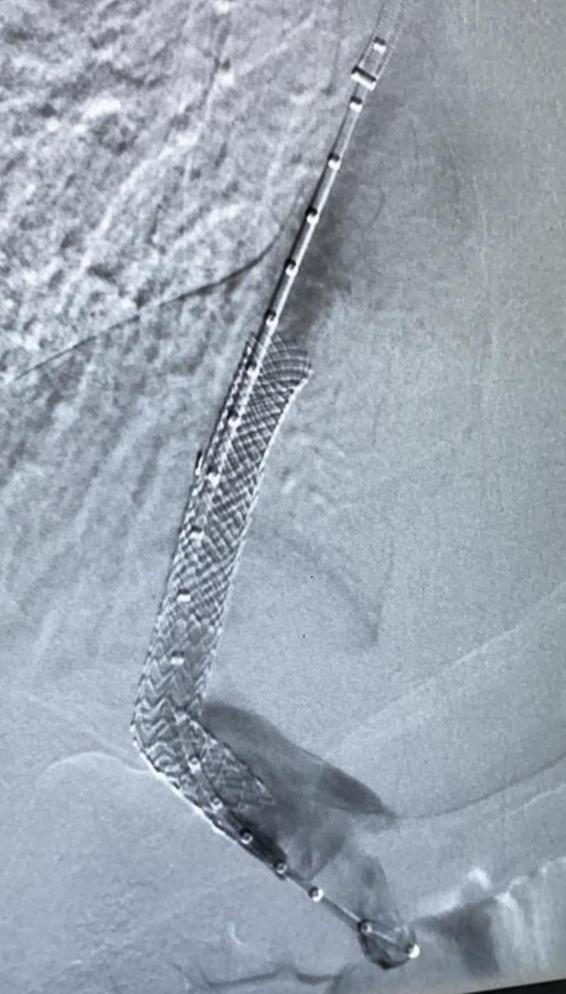

وبعد إستقرار حالة المريض تم تحويله إلى قسم الأشعة التداخلية والقسطرة حيث تمكن الفريق الطبي المختص من إجراء القسطرة وتركيب دعامة بين الوريد البابي والوريد الكبدي وذلك في عملية أستغرقت 5 ساعات وتكللت بالنجاح ولله الحمد.